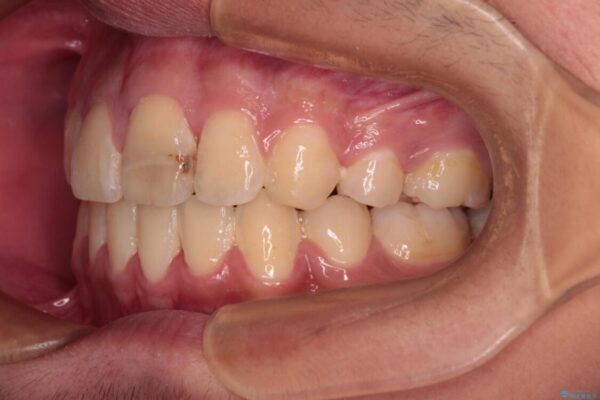

治療前

• 膨らんだ口元 ワイヤー装置での抜歯矯正 治療前画像